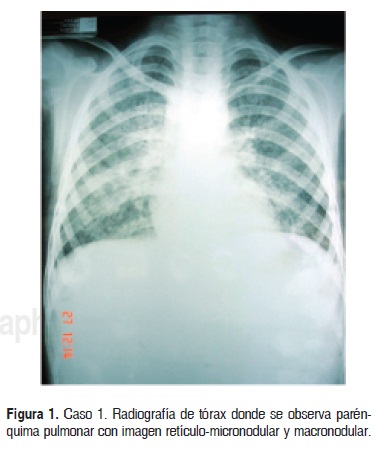

Caso 1. Paciente del sexo femenino de 11 años de edad, originaria y residente de Zimapam, Hidalgo, que se encontraba hospitalizada en una institución de tercer nivel con diagnóstico de neumonía (Fig. 1). Se solicitó interconsulta al Servicio de Dermatología por presentar dermatosis diseminada bilateral y simétrica, que afectaba las comisuras de la boca, cuello, pliegues axilares, antecubitales, inguinales y vulva; la dermatosis estaba constituida por grandes placas mal definidas, conformadas por eritema, costras melicéricas y hemáticas, exulceración y piel de aspecto eccematoso; en otras áreas predominaba la liquenificación, las costras hemáticas y la hiperpigmentación residual. A nivel axilar e inguinal había aumento de volumen y fístulas con salida de material purulento sin aumento de temperatura o eritema local (abscesos fríos) (Fig. 2). Presentaba desnutrición con peso de 23 kg y talla de 125 cm; a nivel de cara con puente nasal ancho y punta redonda (Fig. 3).

Con estos datos se consideró inidalmente el diagnóstico de eccema atópico; sin embargo, llamaba la atención el antecedente de dos hospitalizaciones a los cuatro y siete años de edad por neumonía, manejada con claritromicina, ketoconazol y cefatoxirma. Además de tener el antecedente de gastroenteritis de repetición desde los cinco años de edad con evacuaciones fétidas y con moco. A los 10 años de edad presentó abscesos fríos en piel y en el año 2005 se le había realizado cultivo de un ganglio inguinal que reportó adiaspiromicosis PAS positiva por Chysosporium parvum. En el año 2006 se le realizó biopsia pulmonar por una imagen radiopaca en radiografía de tórax, reportando lesión granulomatosa. La intradermorreacción con PPD fue negativa.